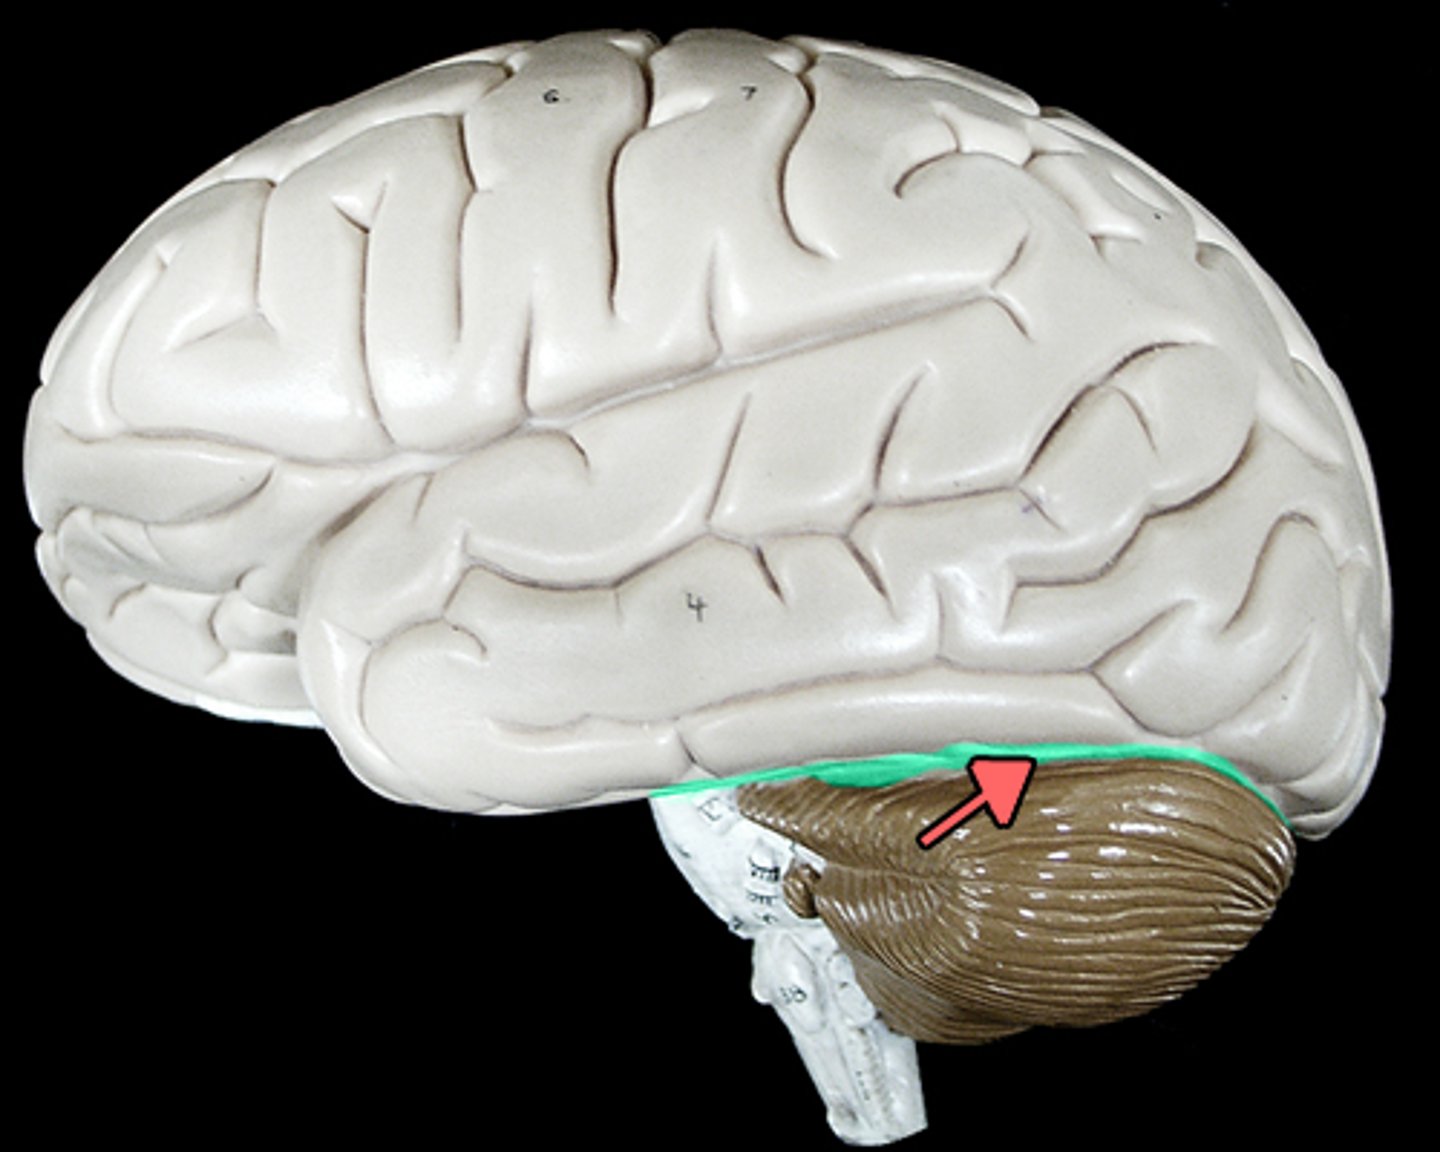

tentorium cerebelli

separates cerebrum from cerebellum

cerebellum

balance, equilibrium, gross motor movement

vermis (cerebellum)

The tissue between the two cerebellar hemispheres

arbor vitae

"tree of life," white matter of cerebellum

transverse fissure

separates cerebrum from cerebellum